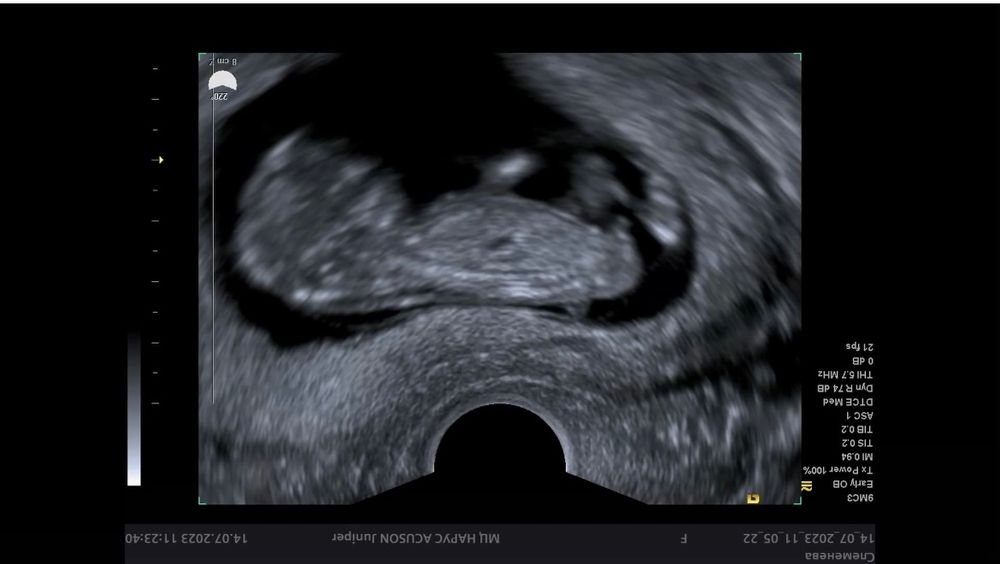

Абсолютно другая картинка другой угол, как у девочки ,а сказали сынок. Так что🤗 главное здоровенький малыш.